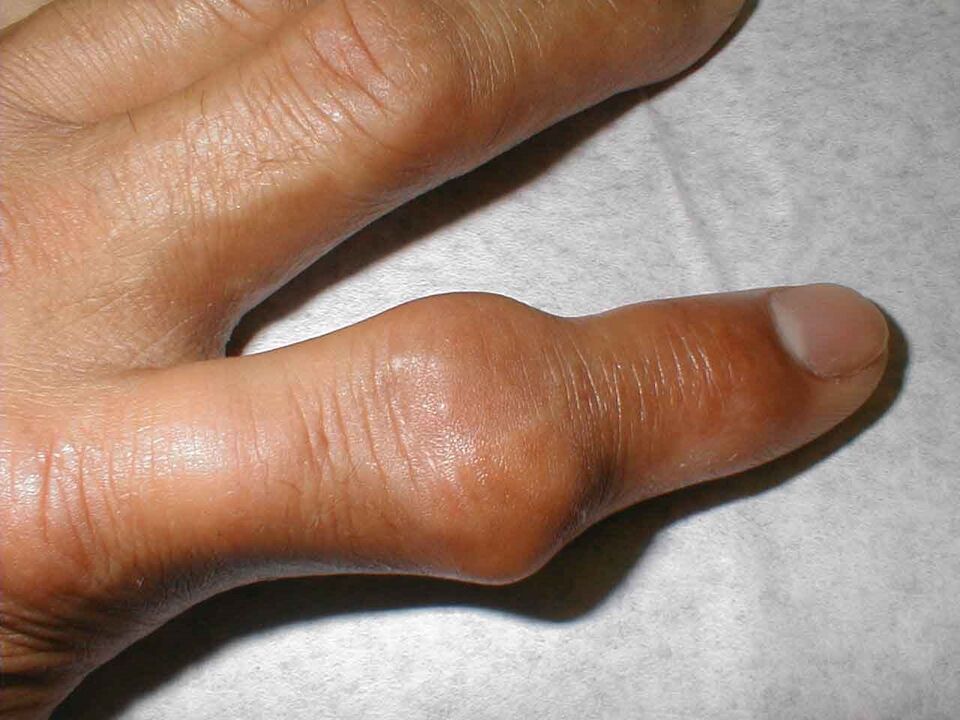

Diese Krankheit betrifft hauptsächlich Männer, da sie eine direkte Folge von Stoffwechselstörungen ist. Der Körper produziert überschüssige Harnsäure, deren Kristalle sich in der Gelenkhöhle ansammeln. Fast immer ist nur ein Gelenk der Hand betroffen und die Erkrankung schreitet sehr schnell voran.

Meistens fühlt sich der Patient beim Zubettgehen absolut gesund. Aber um drei oder vier Uhr morgens wacht er aus unerträglichen Schmerzen in einem geschwollenen Gelenk auf – das ist ein klassisches Bild von Gicht.

Das Gelenk vergrößert sich und wird rot. Es ist unmöglich, es zu berühren, und Schmerzmittel helfen wenig. Dieses starke Schmerzsyndrom wird durch die Ansammlung scharfer Salzkristalle (Urate) in der Gelenkhöhle verursacht, die sich bei jeder Bewegung in die Weichteile eingraben und diese verletzen.

Auch nach einer Normalisierung des Harnsäurespiegels im Körper sieht das Gelenk noch lange Zeit etwas vergrößert aus. Anschließend ist er es oft, der erneut den nächsten Krankheitsschub erlebt.